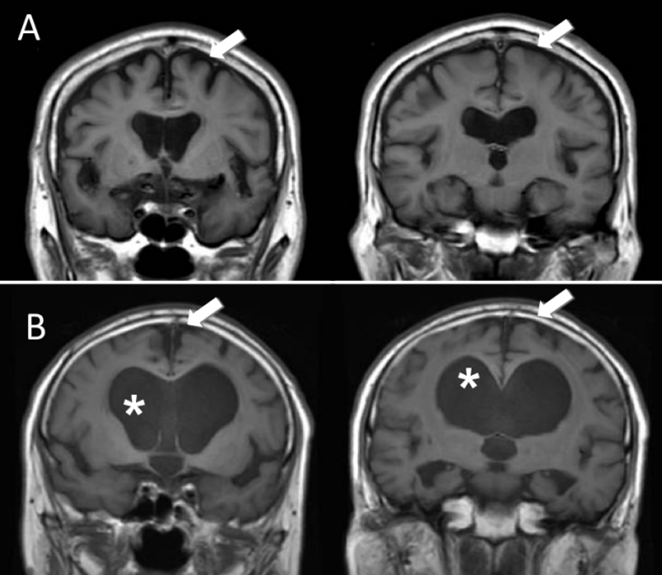

蛛网膜下腔扩大+脑室成比例扩大是脑萎缩的典型影像学特征(图4A)。脑室异常扩大,但蛛网膜下腔未被挤压变窄是慢性梗阻性脑积水的特征(图4B)4。

图4A:脑萎缩:箭头所示的蛛网膜下腔扩大,与脑室扩大(脑室增宽)的程度是成比例的。B:慢性梗阻性脑积水:星号所示的脑室显著扩大,但箭头所示的顶部及内侧蛛网膜下腔仍处于开放/未受压状态(图源:参考文献[4])